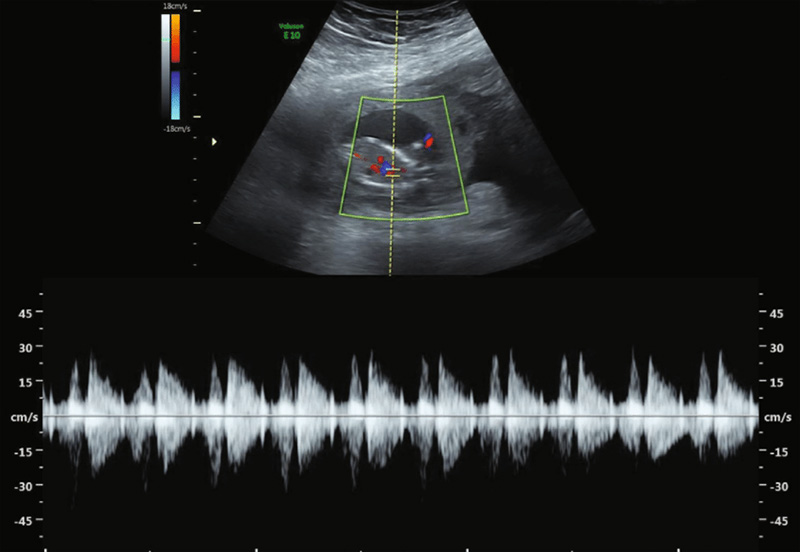

تصویربرداری دو بعدی هنوز استاندارد طلایی است و معمولاً در اکوکاردیوگرافی جنین استفاده می شود. بنابراین، ما نماهای استاندارد از قلب طبیعی جنین را که در سه ماهه دوم با سونوگرافی دو بعدی و داپلر موجی رنگی و پالسی به دست آمده است، ارائه می کنیم. ما همچنین یافتههای اکوکاردیوگرافی جنین در سه ماهه اول و یک شاخص عملکرد قلب اصلاح شد را ارائه میکنیم که ابزار مفیدی برای ارزیابی عملکرد قلب جنین است.

همچنین پزشک جریان خون را در قلب جنین به شما نشان می دهد. این نگاه عمیق به پزشک اجازه می دهد تا هر ناهنجاری در جریان خون یا ضربان قلب نوزاد وجود دارد را بیابد.

جریان در طول دریچه های دهلیزی باید با داپلر رنگی بررسی شود. جهت جریان از دهلیز به بطن است. در هر دو سوپاپ یکسان است. هیچ نام مستعاری نباید دیده شود.

۳.اکوکاردیوگرافی داپلر (Doppler)

اکوکاردیوگرافی داپلر برای ارزیابی جریان خون در قلب و عروق جنین استفاده میشود. این روش برخلاف دو نوع قبلی که تمرکز بر ساختارهای فیزیکی قلب دارند، بیشتر به بررسی عملکرد قلب از نظر جریان خون میپردازد.

در این نوع تصویربرداری، پزشک میتواند سرعت و جهت جریان خون را اندازهگیری کند. این اطلاعات نقش کلیدی در تشخیص مشکلاتی مانند نارسایی قلبی، تنگی یا نارسایی دریچهها، و اختلالات در دهلیزها و بطنها دارد. در صورتی که پزشک به وجود ناهنجاری در گردش خون جنین مشکوک شود، استفاده از اکو داپلر بهعنوان ابزار تشخیصی الزامی خواهد بود.

اکوکاردیوگرافی داپلر: این تکنیک داپلر برای اندازه گیری و ارزیابی جریان خون از طریق اتاقک ها و دریچه های قلب استفاده می شود. داپلر همچنین میتواند جریان خون غیرطبیعی در قلب را تشخیص دهد که میتواند مشکلاتی مانند باز شدن بین حفرههای قلب، مشکل یک یا چند دریچه از چهار دریچه قلب یا مشکل دیوارههای قلب را نشان دهد.

داپلر رنگی داپلر رنگی شکل پیشرفته اکوکاردیوگرافی داپلر است. با داپلر رنگی، از رنگ های مختلف برای تعیین جهت جریان خون استفاده می شود. این کار تفسیر تصاویر داپلر را ساده می کند.